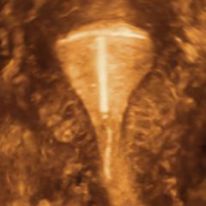

IUDs that fit properly have the least risk to cause side effects. Both the TCu380A IUD (Paragard®), left, and the Mirena® LNG-IUS have a transverse arm length of 32 mm. If the uterine cavity is wide enough, the risk of pain, bleeding expulsion and embedment is low.

Frameless copper IUDs are designed to optimize intrauterine contraception The uterine cavity width is the most important parameter relate...